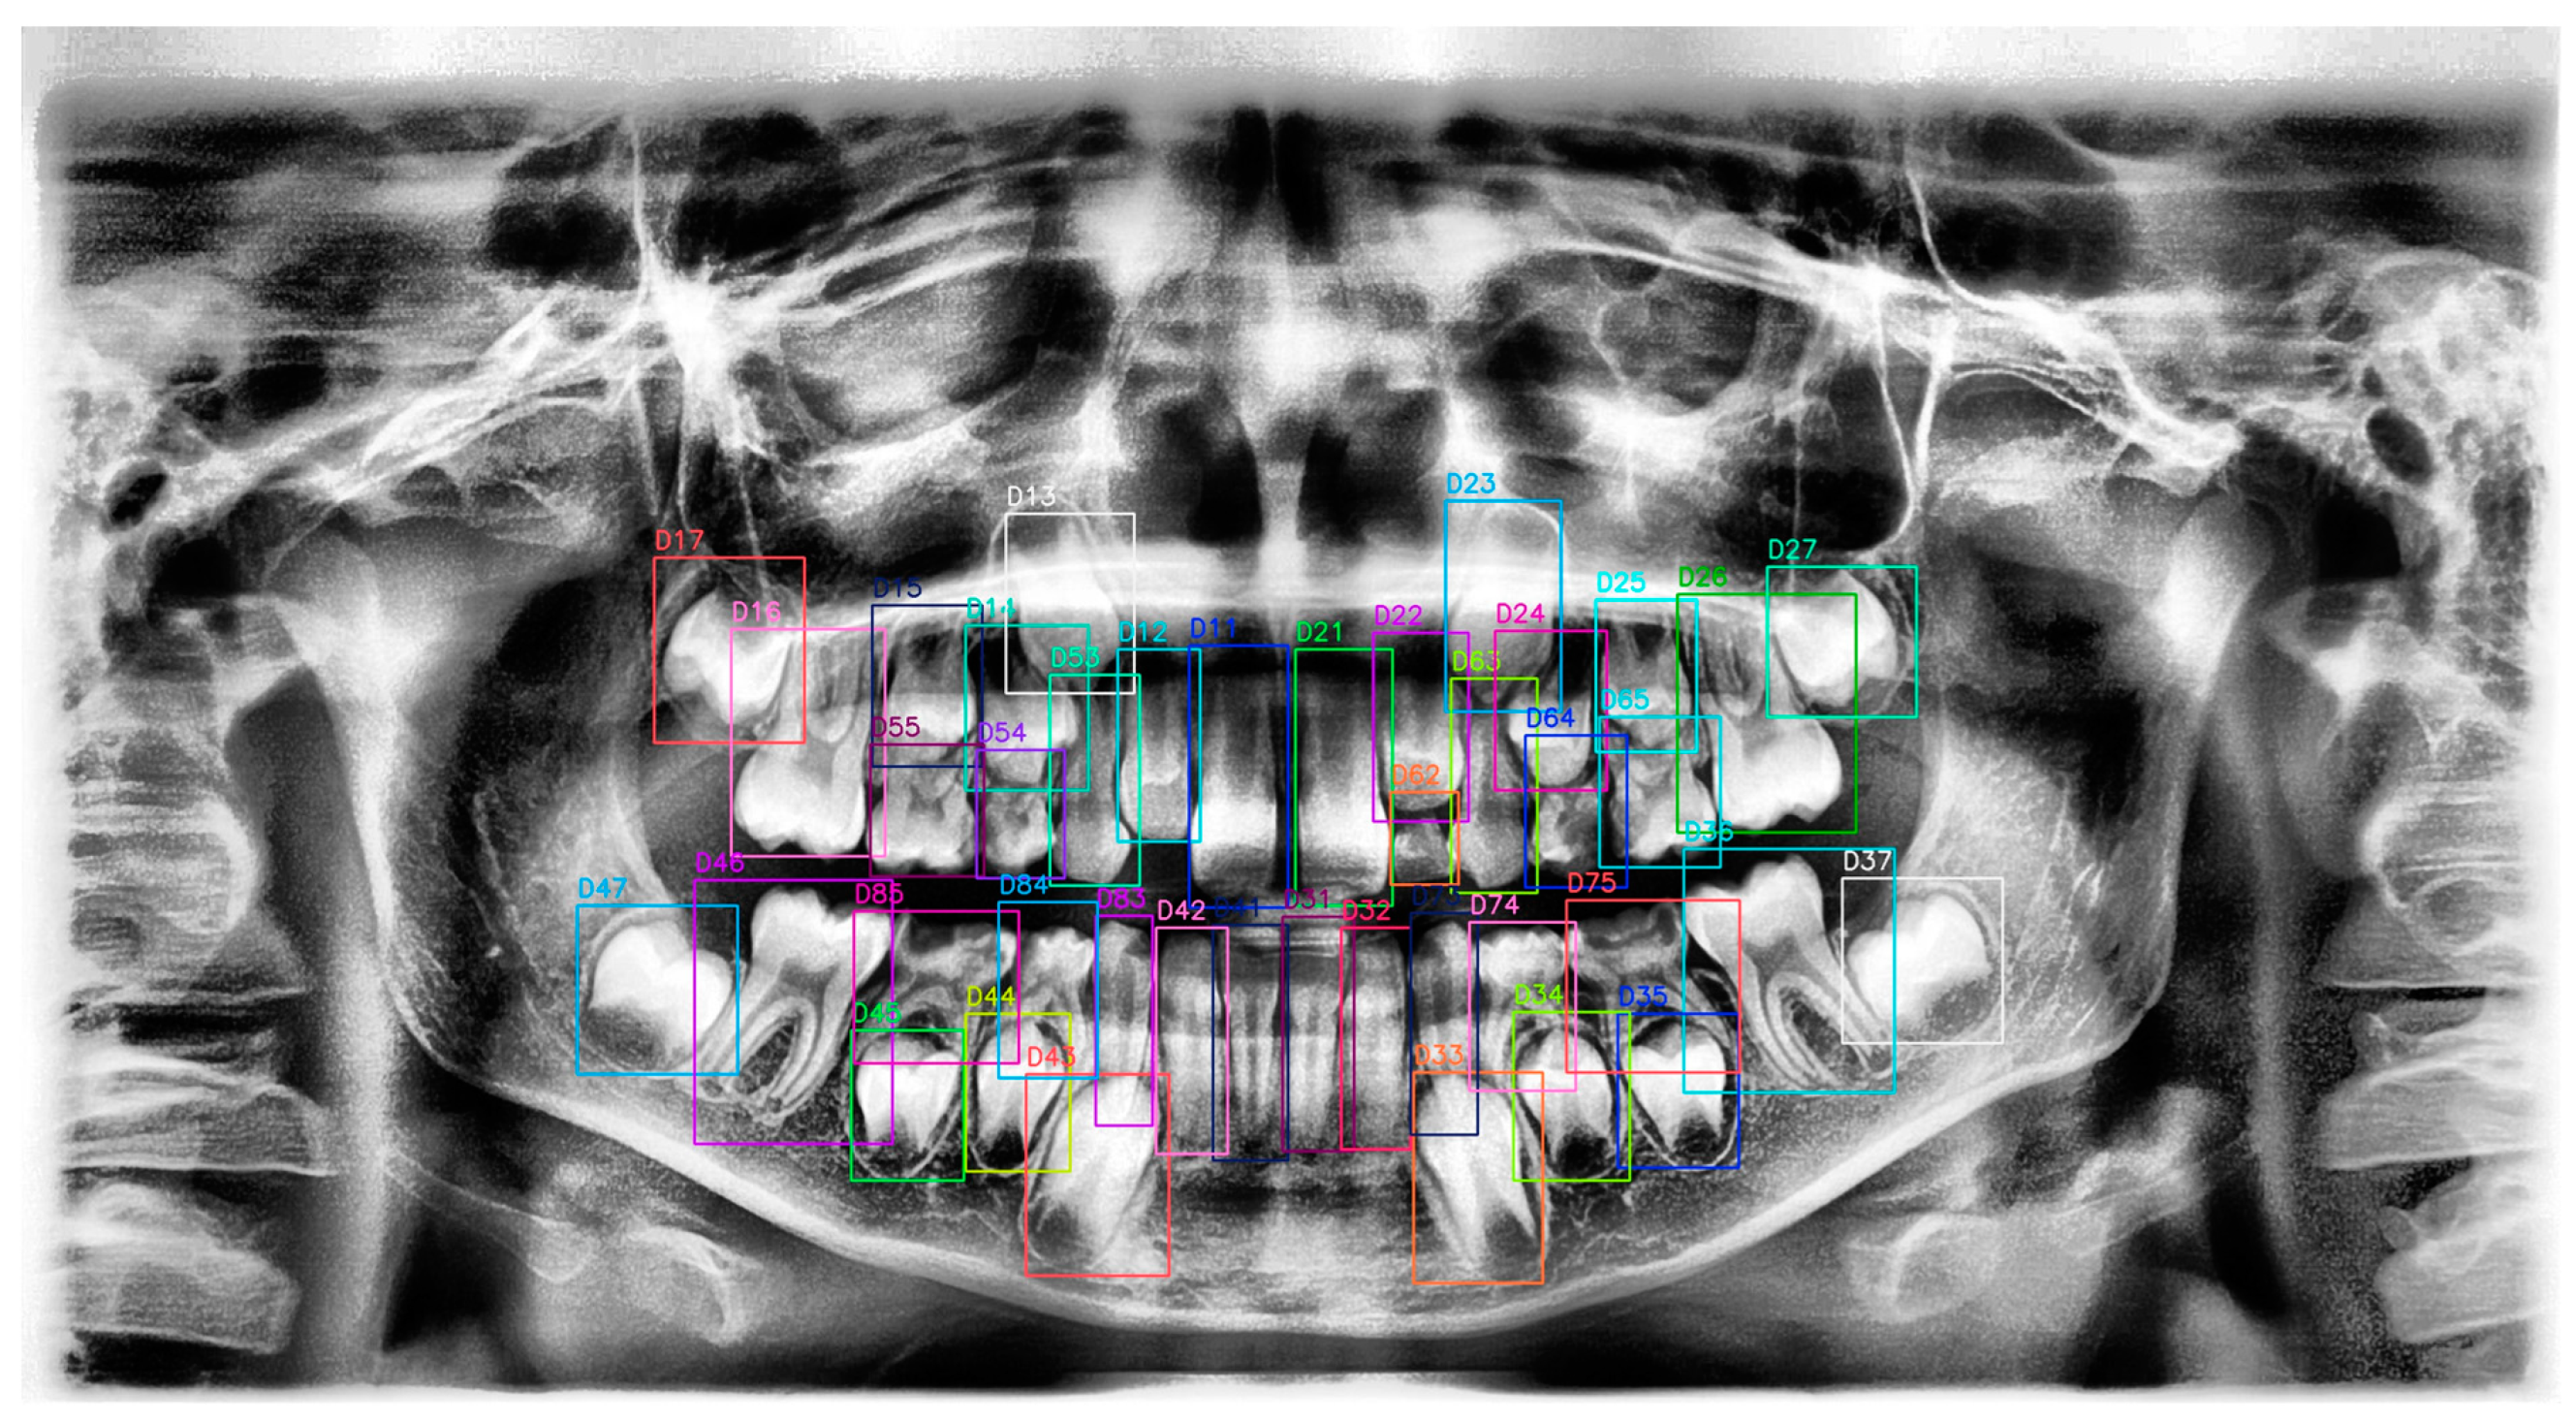

2.4. Ground Truth Labeling